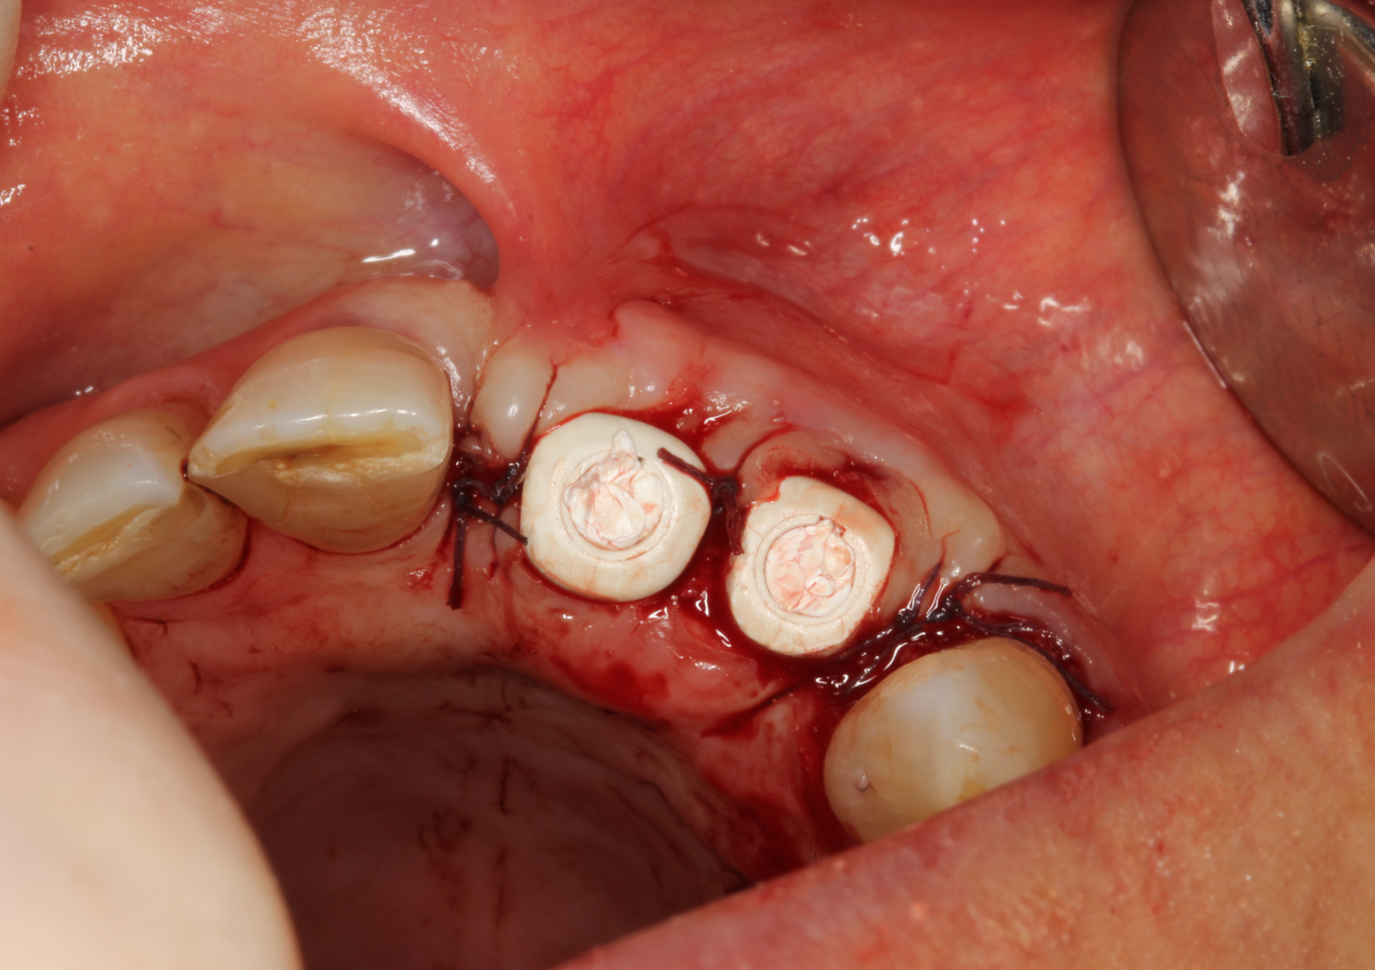

Figure 1.

Two 4.0 × 13 mm Neoss ProActive® Tapered implants were placed in position 11 and 12. Two Esthetic Healing Abutment – Incisor (wide and narrow) were placed before positioning bone substitute to augment the buccal volume.